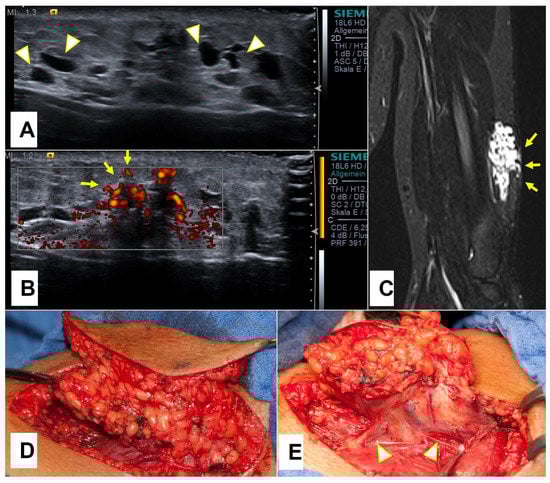

All SGA patients received an ultrasound examination (US) at their first encounter. On the US, SGA were described as nonspecific mass(es) with interacting hypo- and hyper-echoic zones, ill-defined borders, and mild hypervascularization (Figure 4).

Figure 4.

Representative slices of ultrasound imaging of subcutaneous granuloma annulare (SGA). The lesions are strictly epifascial with hypo- and hyper-echogenic zones and mild hypervascularization. A common finding is the cap shape of these lesions, marked with arrowheads. The depicted lesions were located on (A) the right forearm; (B) the right lower leg; (C) the left lower leg; (D) the right lower leg.

On ultrasound, an SGA appears as an epifascial subcutaneous soft tissue mass, hypoechogenic in the center, with a hyperechoic zone in the periphery and mild vascularization. This lesion projects over the surface of the muscle’s fascia without invading it. Supposing that during the ultrasound evaluation, it is possible to recognize the epifascial cape shape of the lesion, we recommend using SGA as your primary working diagnosis and referring the child for a clinical follow-up with a repeat US of the lump in 4 weeks (Figure 12).